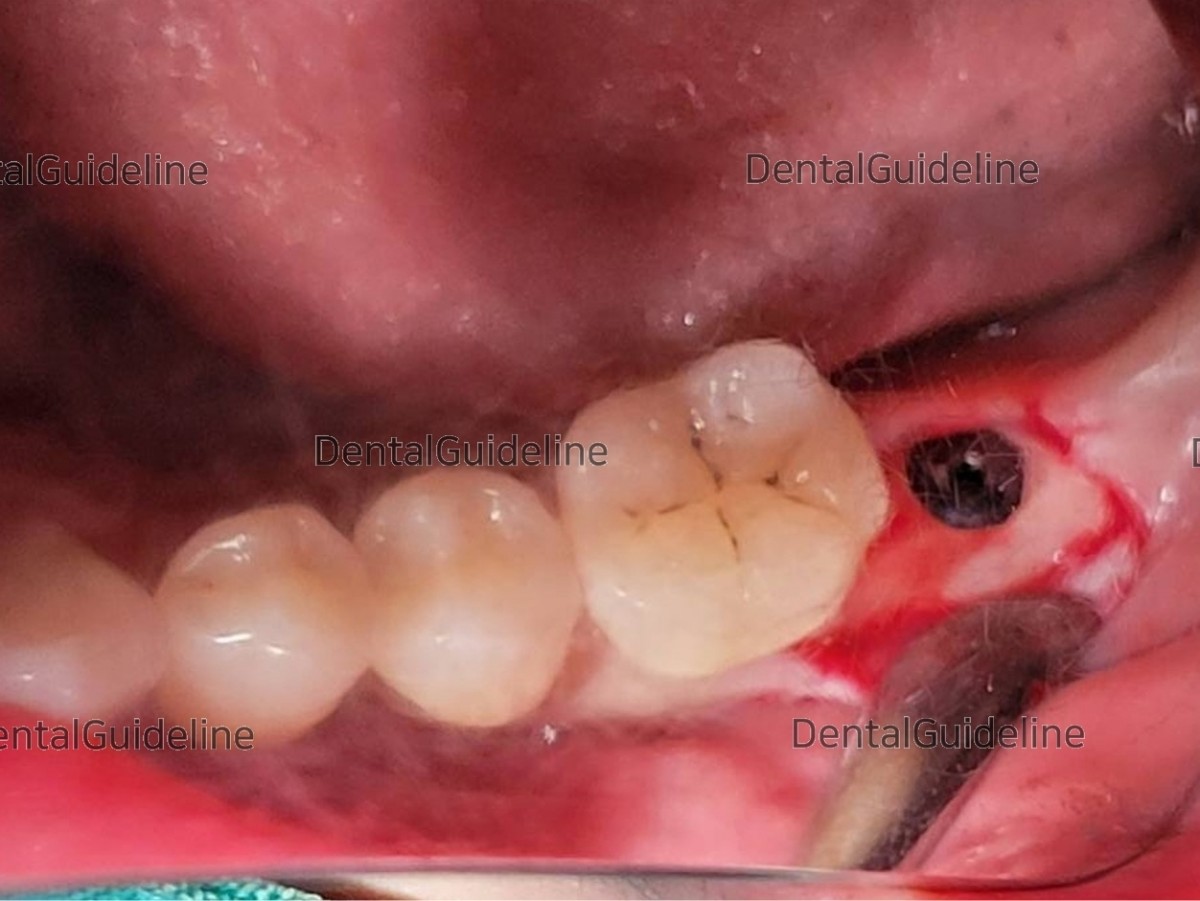

5. Serial osteotomy and placement of the implant (Arum Dentistry Co. NB1 Ø4.5/L10, 30Ncm).

6. A collagen membrane was used to protect the surgical site.

10. A linear incision was given on the attached gingiva to secure the attached gingiva.

11. Healing Abutment engagement by expanding soft tissue to form the dense sulcus of the gingiva.